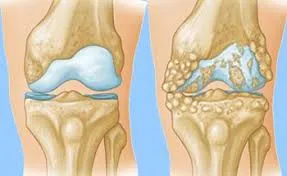

膝關節就像是車子的輪胎與避震器。健康的膝蓋骨頭表面覆蓋著一層光滑的「關節軟骨」,中間還有負責緩衝的「半月板」與潤滑的「關節液」。

軟骨磨損 (Wear and Tear): 隨著年齡增長或長期負重,軟骨就像磨平的輪胎皮一樣變薄、變粗糙,失去緩衝能力。

骨刺增生 (Bone Spurs): 為了增加接觸面積來分擔壓力,骨頭邊緣會長出贅骨(骨刺)。骨刺本身不一定會痛,但它代表關節已經不穩定了。

發炎反應: 磨損的碎屑掉在關節腔內,會刺激滑膜發炎,導致關節積水腫脹(膝蓋看起來腫腫的),這就是疼痛的主要來源。